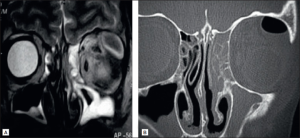

As a brief overview, the extension of sinus infections into the orbit region is characterized by early thickening of the medial rectus, followed by involvement of other extraocular muscles1. Bone erosion of the lamina papyracea and orbital walls, stretching and thickening of the optic nerve, and spread of soft tissue inflammation to the orbital fissures and apex can show worsening of the condition. Cavernous sinus infection would present with altered intensity of the cavernous sinus on MRI. An MRI can also assess for lobar involvement, namely the basifrontal and temporal lobes, and large vessel narrowing.

As previously mentioned, orbital symptoms of sinusitis are often due to the progression of untreated or fast-developing invasive sinusitis. In the case of fungal sinusitis, diagnostic steps consider several variables including history, presentation, imaging, endoscopic biopsy with histopathology, and laboratory findings11. Contrast imaging with CT or MRI are the gold standard for diagnostic measures3. One study found that 91% of cases were diagnosed correctly with CT compared to 82% diagnosed clinically4.

However, it is important to note that many new growing abscesses may not have obvious signs on a contrast-CT, with only non-specific signs of inflammation. In the case of orbital abscesses, normal CT scans have been seen to miss the presence of abscess27. Many authors have noted initial orbital biopsies fail to identify the species of fungus, with repeat incisional biopsies necessary to confirm.